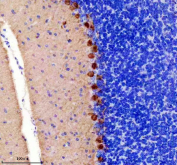

Immunohistochemical staining of rat cerebellum using PRKCG antibody, HRP-secondary and DAB substrate. HIER: boil tissue sections in pH8 EDTA for 20 min and allow to cool before testing. Protein kinase C gamma shows strong cytoplasmic staining in Purkinje neurons localized to the Purkinje cell layer, with minimal staining in the surrounding granular layer.

Immunohistochemical staining of mouse cerebellum using PRKCG antibody, HRP-secondary and DAB substrate. HIER: boil tissue sections in pH8 EDTA for 20 min and allow to cool before testing. Protein kinase C gamma shows strong cytoplasmic staining in Purkinje neurons localized to the Purkinje cell layer, with minimal staining in the surrounding granular layer.